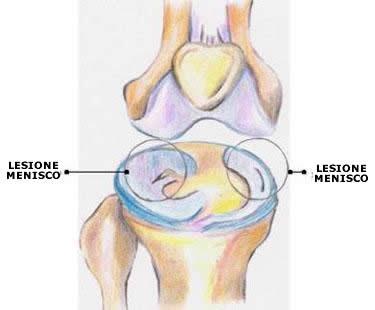

Si verifica tale situazione allorchè si lesiona quella parte del ginocchio, che consiste in una struttura cartilaginea situata tra femore e tibia, la cui funzione è quella di distribuire meglio il carico sull’articolazione e determinare il funzionamento del movimento. Se, insieme alla rottura del menisco, si verifica anche la rottura dei legamenti del ginocchio o del crociato, la gravità è sicuramente peggiore. La rottura del menisco può essere mediale o laterale. Sintomatologia del fenomeno è sicuramente il dolore insieme al rigonfiamento topico. Il dolore, nel caso del menisco mediale, è avvertito nella parte interna del ginocchio; nel caso del menisco laterale, invece, il dolore è localizzato esternamente. In ambedue i casi si verifica un cedimento ed anche un blocco dell’articolazione del ginocchio. Ciò avviene perché frammenti di menisco si inseriscono nelle parti che determinano la mobilità del ginocchio. Se avviene una pressione o una rotazione, il dolore tende ad aumentare e non si può estendere l’articolazione completamente. Inoltre viene prodotto del liquido, che si va ad accumulare nell’articolazione, a causa dell’infiammazione. L’articolazione subisce uno scricchiolio, oltre ad una perdita di forza del quadricipite.